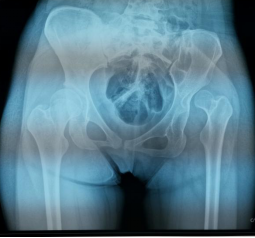

通过小张的骨盆X线可以看到,她的左侧髋臼是一个发育不良的状态,髋臼较小较浅,外展角较大,而股骨头已经完全脱位,根据脱位高度分型为DDH(developmental dysplasia hip,发育性髋关节发育不良)IV型,已经属于最严重的程度了。

(下肢不等长,Allis征+) (骨盆正位片)